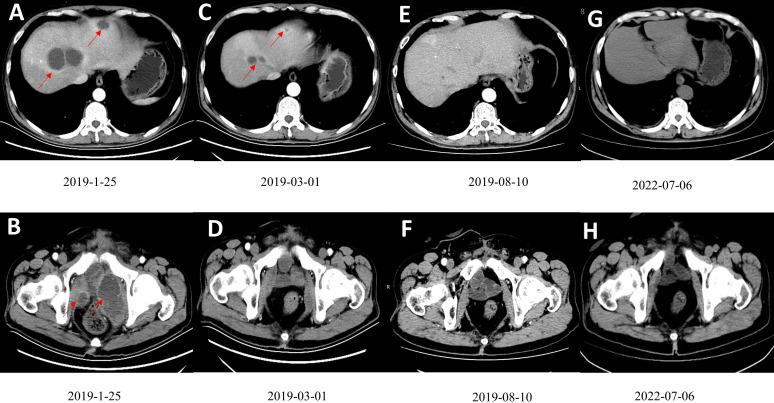

This article described a patient with metastatic bladder cancer (mBC) who was successfully treated with nab-paclitaxel plus sintilimab. Localized muscle-invasive bladder cancer (MIBC) was discovered in a 56-year-old man who received radical cystectomy and platinum-based adjuvant chemotherapy. Eleven months after cystectomy, this patient developed numerous hepatic and pelvic metastases and progressed to mBC. The patient was given an anti-PD-1 antibody (sintilimab 200mg, q3w) in combination with Nab-paclitaxel (100mg, qw) for mBC. Complete remission (CR) was achieved after nine cycles of therapy, and the patient had no severe side effects during the treatment. The disease remained in CR after 41 months of follow-up. This case suggests that nab-paclitaxel combined with sintilimab is a safe and effective option in treatment of mBC.

本文描述了一名转移性膀胱癌(mBC)患者,其接受纳米白蛋白结合型紫杉醇联合信迪利单抗治疗取得成功。一名56岁男性被诊断为局限性肌层浸润性膀胱癌(MIBC),接受了根治性膀胱切除术和铂类辅助化疗。膀胱切除术后11个月,该患者出现大量肝转移和盆腔转移,病情进展为mBC。给予该患者抗PD-1抗体(信迪利单抗200mg,每3周一次)联合纳米白蛋白结合型紫杉醇(100mg,每周一次)治疗mBC。经过9个周期的治疗实现了完全缓解(CR),且患者在治疗期间未出现严重副作用。随访41个月后,疾病仍处于CR状态。该病例表明,纳米白蛋白结合型紫杉醇联合信迪利单抗是治疗mBC的一种安全有效的选择。